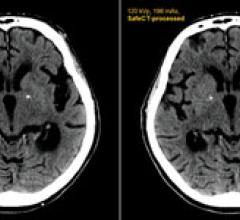

January 5, 2011 — The U.S. Food and Drug Administration (FDA) has given clearance for Medic Vision Ltd. to market its…